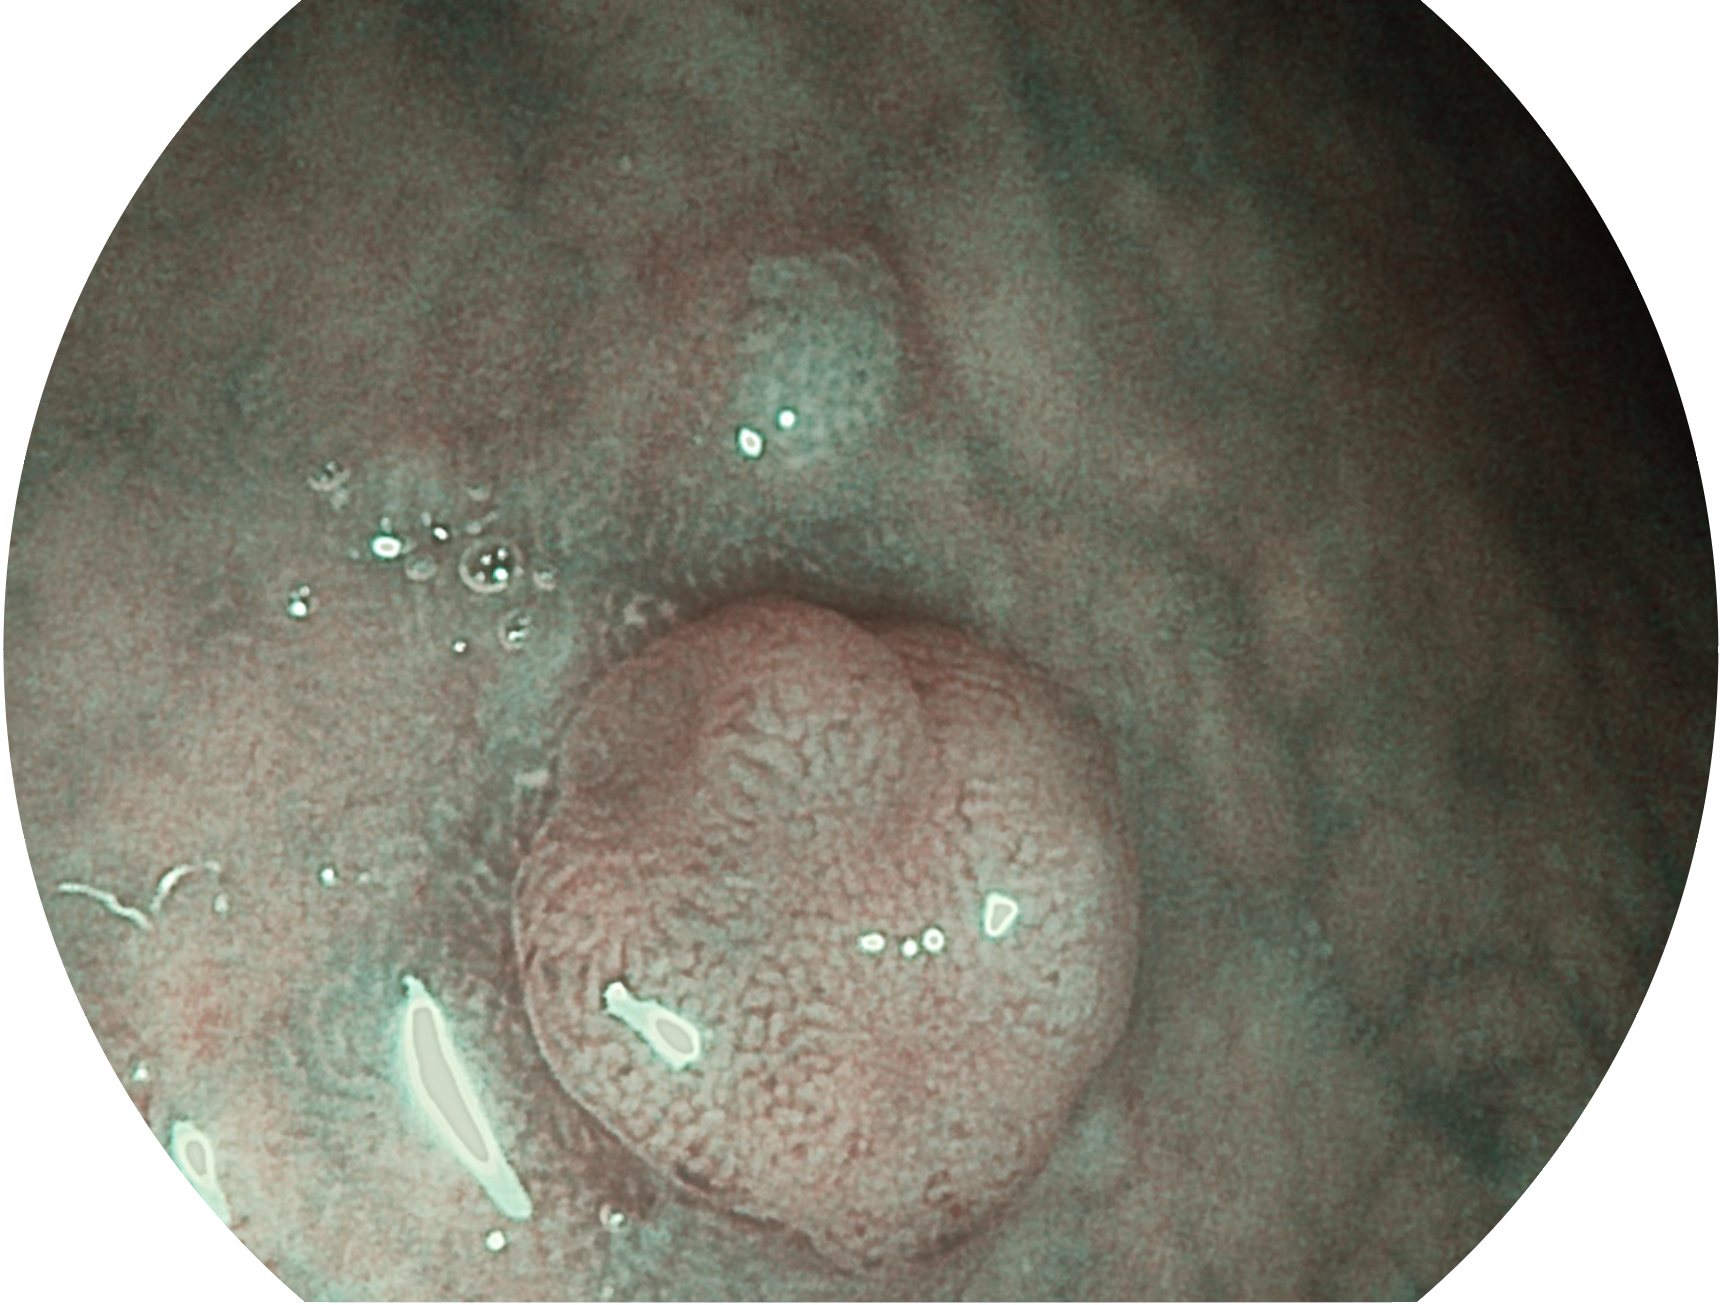

開(kāi)立新開(kāi)發(fā)的內(nèi)鏡染色技術(shù),主要是基于多波長(zhǎng)LED 光源的開(kāi)發(fā),VLS-55Q 四波長(zhǎng)LED 光源是由四個(gè)不同顏色的LED光按照相應(yīng)照明模式所規(guī)定的特定發(fā)光比例進(jìn)行合束后形成,合束后形成的照明光的光譜由紅光、綠光、藍(lán)光及藍(lán)紫光這四個(gè)不同的波段范圍構(gòu)成。具有更高光譜自由度,通過(guò)光譜比例的控制,實(shí)現(xiàn)了聚譜成像技術(shù),英文全稱為“Spectral Focused Imaging, SFI”,縮寫為“SFI”和光電復(fù)合染色成像技術(shù),英文全稱為“Versatile Intelligent Staining Technology, VIST”,縮寫為“VIST”。